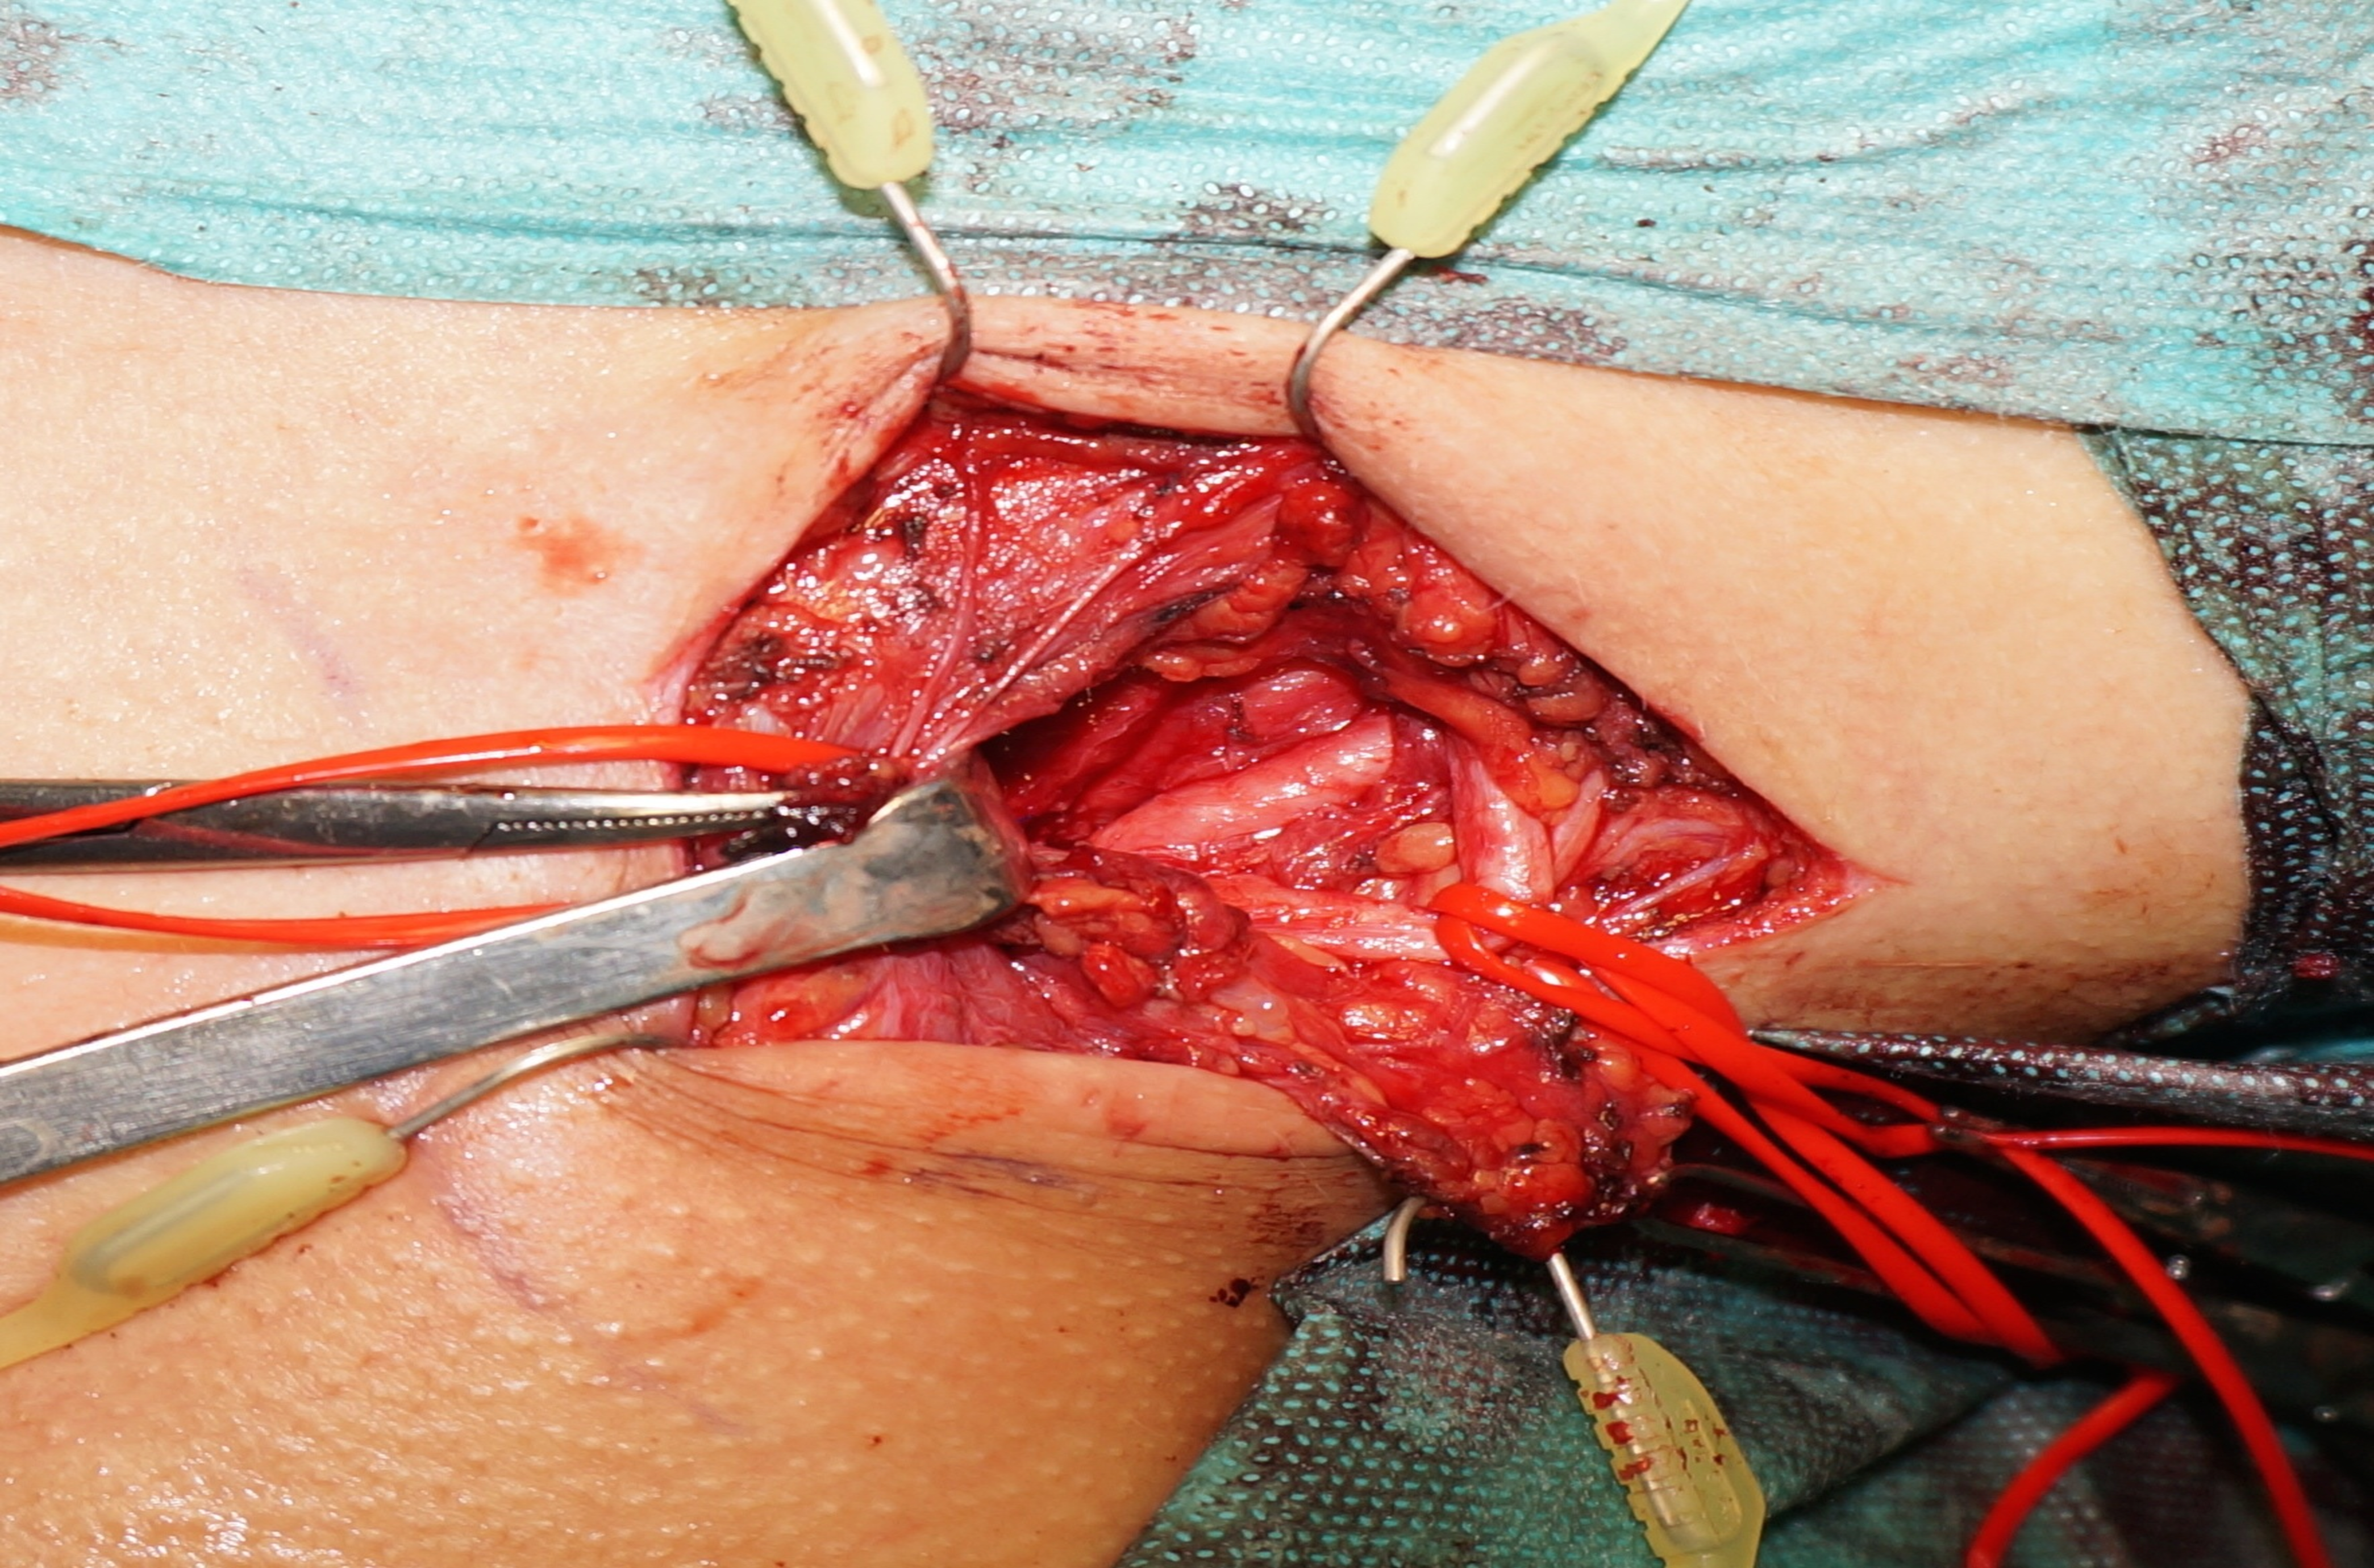

Next, the anterior and middle scalene muscles were divided from the first rib. The 3 trunks of the brachial plexus were visualized and gently protected. A supernumerary anomalous rib with a 90-degree curvature was unveiled, which was articulated to the first costal arch. Compression of the inferior trunk of the brachial plexus and the subclavian artery was obvious (Figure 4). The first rib was encircled and divided (Figure 5). It was decided not to remove the posterior edge of the first rib because of the iatrogenic risk of C8 root damage. The SCM muscle was repaired, and the wound was closed in a subcuticular fashion over a suction drain. The postoperative period was uneventful, and the patient was discharged home on the third day postoperative.

Figure 5. After division of the first rib: note the normal anatomical position of the inferior trunk at the end of the surgery.